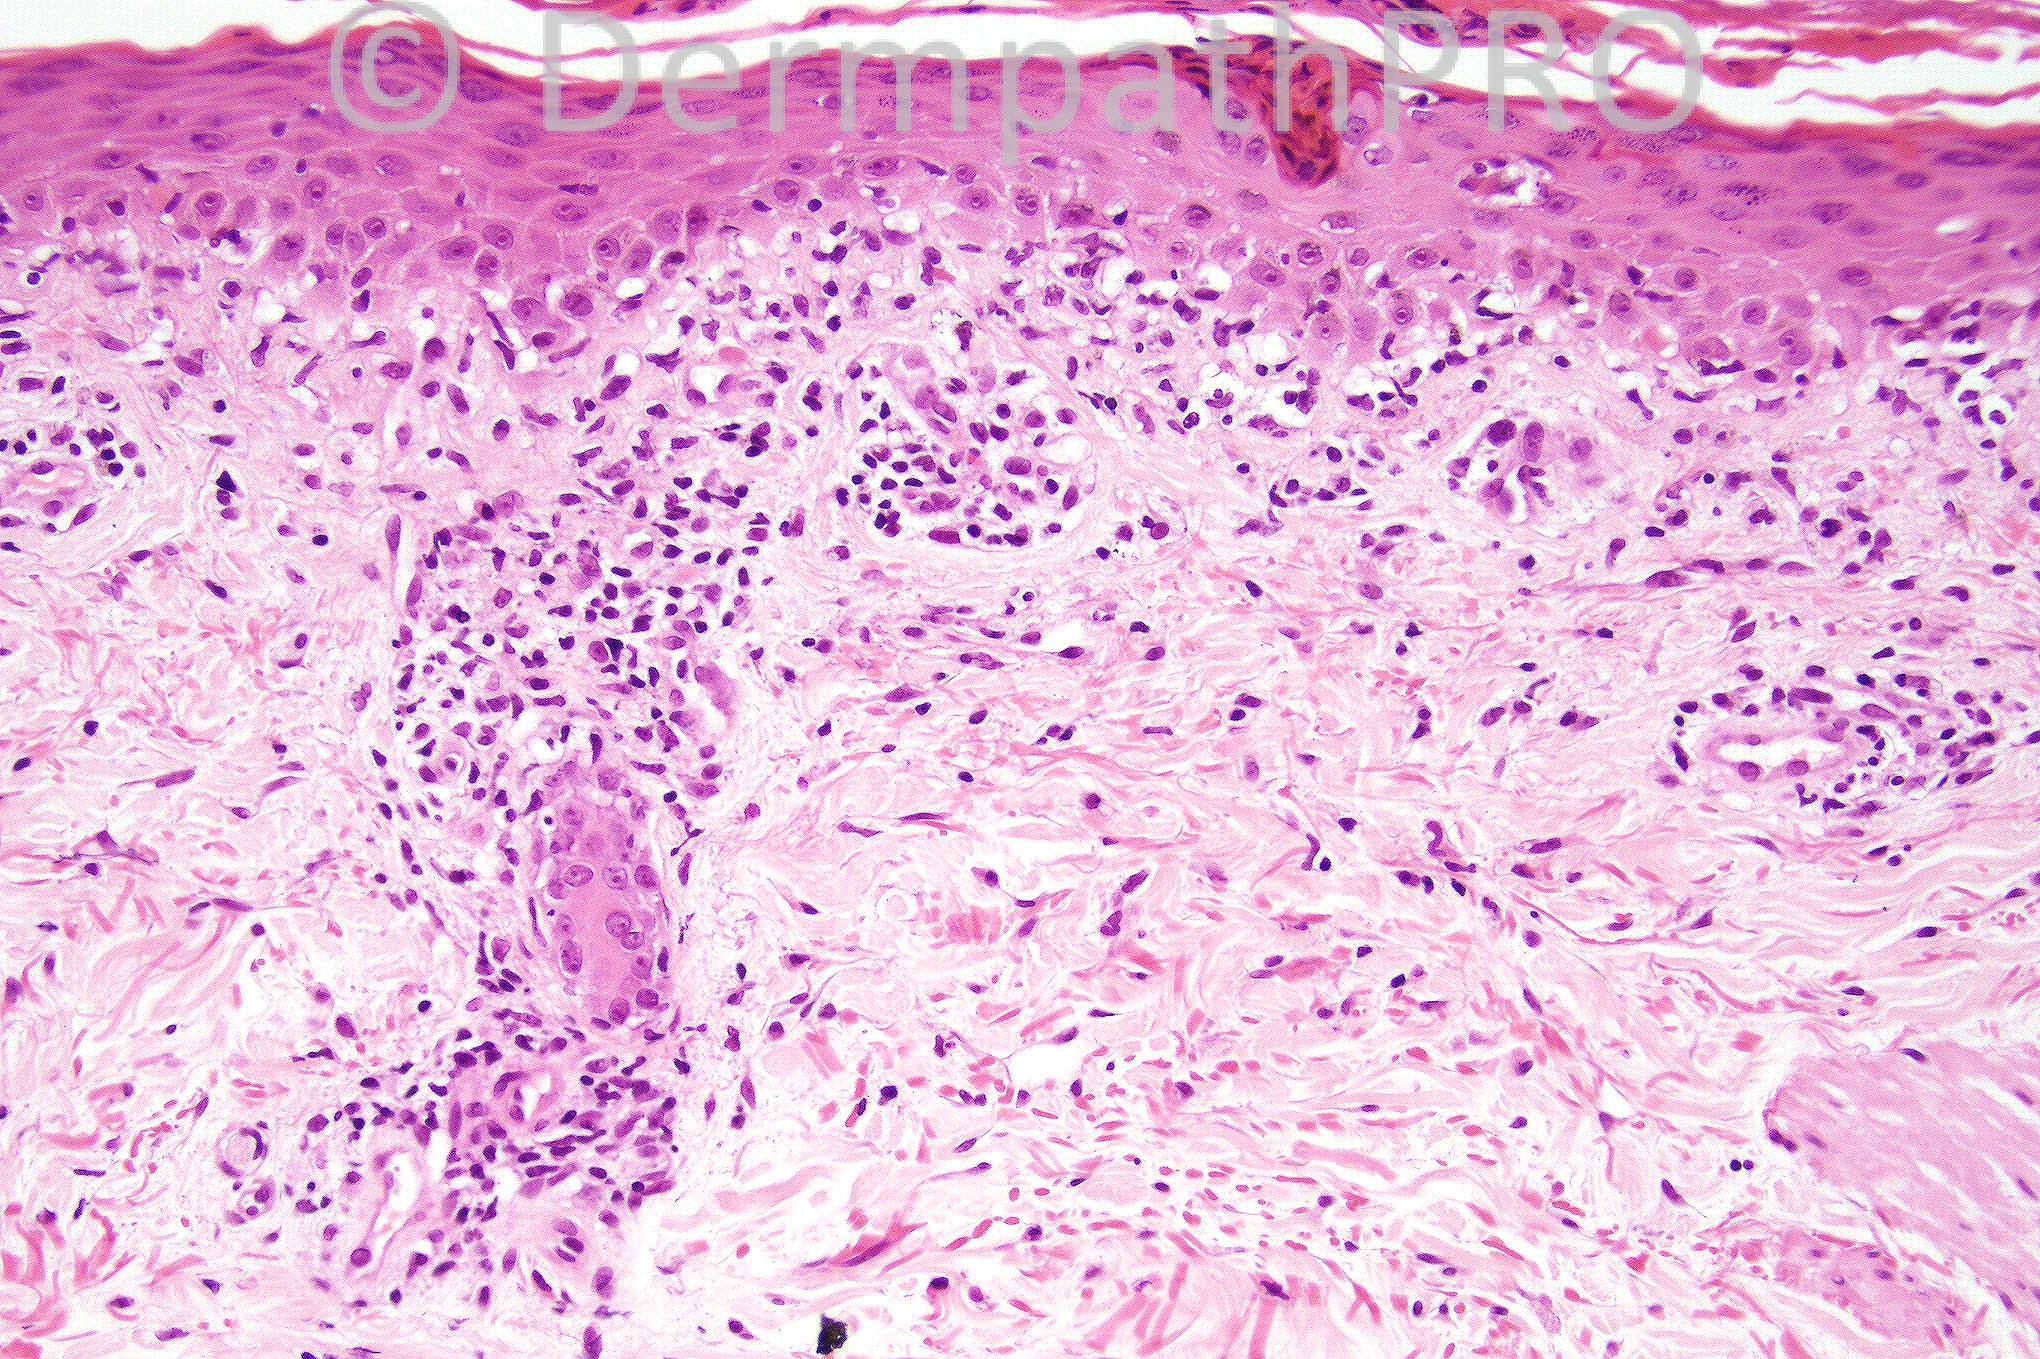

Female 32 years with a history of widespread erythematous macules some with a central papule and/or vesicle formation. Oral lesions were also present.